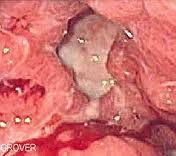

Peptic Ulcer definition

tissue damage with impaired healing- in epigastric area.

Gastric presentation of Peptic ulcers

Gastric pain, hemorrhage in 25% - looks like coffee grounds - Anorexia, nausea, vomiting, pain 30 minutes after eating

Duodenal presentation of peptic ulcers

Burning, gnawing or vague Epigastric pain; worse 2-3 hours after eating; pain is better with food or antacids.

Medical treatment of peptic ulcers

Antibiotics for H. pylori, bismuth, histamine and acid-reducters

Massage considerations for peptic ulcers

avoid pressure to abdomen; avoid prone position; caution with working on abdomen; watch for dizziness when getting up from table; Parasympathetic intent can increase mucus barrier